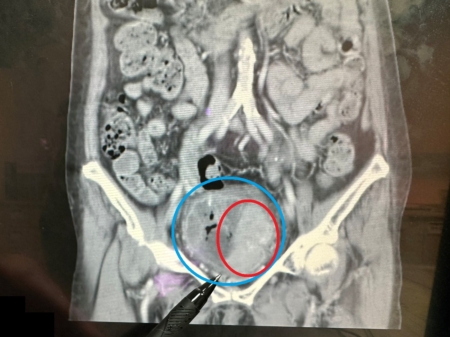

進一步安排靜脈注射腎盂攝影,顯示在膀胱內有大片陰影,續以膀胱鏡檢查,發現膀胱內有一個約7×6公分的巨大腫瘤。所幸,經醫師安排「經尿道膀胱腫瘤刮除手術」後,順利清除腫瘤,也成功保留膀胱,目前恢復良好並定期回診追蹤。

大千綜合醫院泌尿科醫師陸兆明表示,此位病人的膀胱腫瘤體積頗大,已占據未漲尿時的膀胱將近1/2空間,但因為腫瘤細胞尚未侵犯到膀胱外圍,也沒有骨盆淋巴結轉移的情況,因此適用「經尿道膀胱腫瘤刮除手術」來處理腫瘤。此手術透過膀胱內視鏡,由尿道進入膀胱來逐步刮除腫瘤,不僅可得到足夠的檢體,來檢查癌細胞有無侵犯深層肌肉,並將肉眼可見的病灶加以切除;同時,病人腹部無傷口,且可保留膀胱,繼續保有儲尿和排尿的功能,不需另裝人工膀胱,就能維持正常生活品質。另外,病人手術後恢復快、併發症少、安全性較高,對於初期膀胱癌的病人而言是一適合的治療選擇。

此次案例先經手術刮除腫瘤後,再輔以放射治療,清除可能殘留於膀胱壁內較深層的腫瘤細胞。術後2天病人恢復良好,大幅改善血尿、解尿疼痛及頻尿感問題。三個月後回診追蹤,病人膀胱內壁已復原、腫瘤消失且沒有骨盆腔淋巴結腫大的情況,後續只需持續定期門診追蹤。